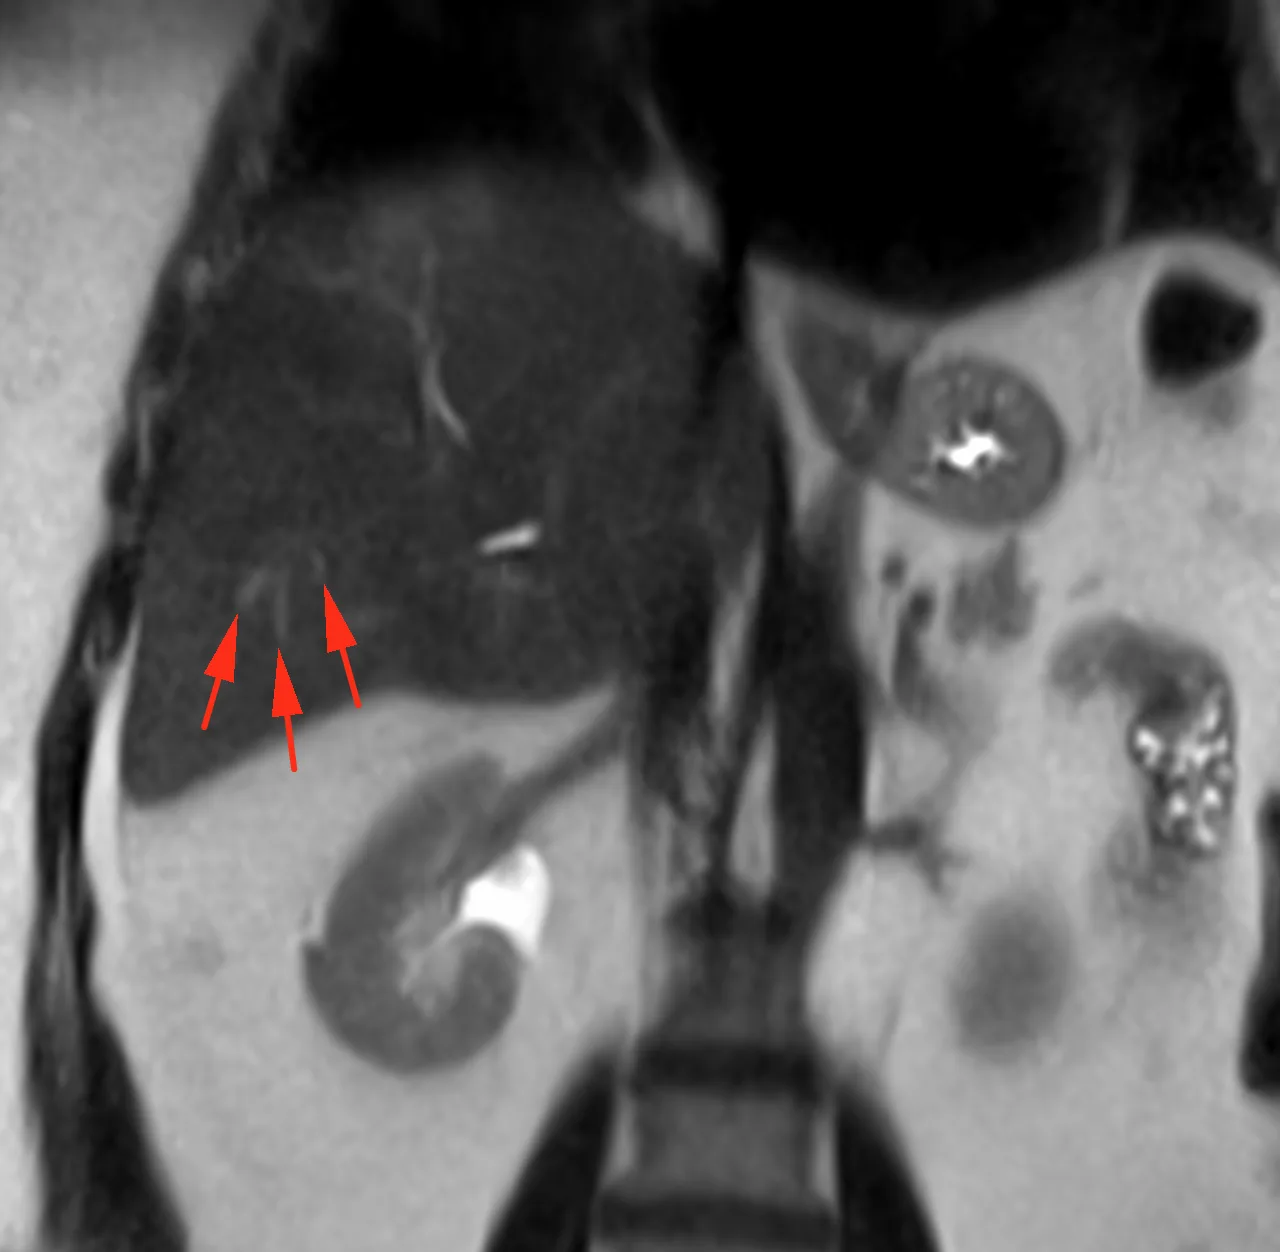

Хороший пример (не верифицирован, но все же, уж больно характерный вид) дифференциальной диагностики множественных новообразований печени. Пациент 63 года. Морфология кольцевидная и на контрастом усиленных сканах, и на диффузии, но не идеально шаровидная, солидный край толстый и неравномерной толщины, артериального гиперконтрастирования больше, чем у паренхимы печени нет (что против гепатоцеллюллярного рака), вымывания нет (тоже против ГЦР), накопление в центре постепенное и медленное. Голосую за периферическую холангиокарциному (или первично множественную, или с внутрипечёночной диссеминацией). А ещё за холангиокарциному - ретракция контура печени и расширение протоков мелких вверх по течению: это достаточно специфично именно для холангиокарциномы. Для гиперваскулярных метастазов нехарактерно отсутствие гиперваскулярности (нет быстрого накопления с вымыванием), на гиповаскулярные, в принципе, паттерн контрастирования, похож, но не похожа морфология (не шарики, не идеальные колечки, ретракция печени, расширение протоков вверх по течению - не характерны для метастазов). Посмотрим, угадаем ли. Но случай интересный. Показательный.